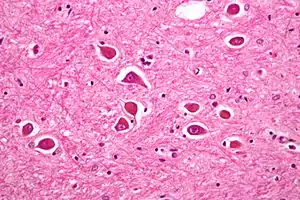

| Micrograph of Alzheimer type II astrocytes, as may be seen in hepatic encephalopathy. | |